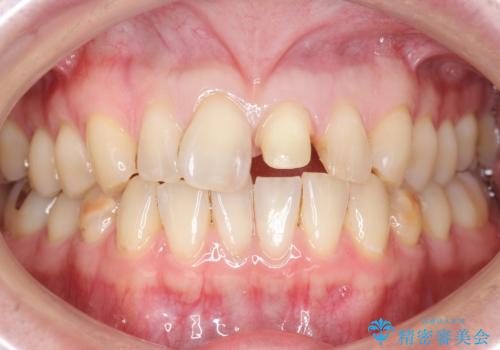

- 前歯のプラスチックの詰め物が気になると来院された患者様です。

左上の前歯に詰められたプラスチック(コンポジットレジン)は、劣化し変色していました。

レジンを除去したところ二次う蝕を認めたため、丁寧に虫歯をとりました。

歯の欠損範囲が大きいことから、同様にレジン修復しても欠けやすいためセラミッククラウンによる補綴を行いました。